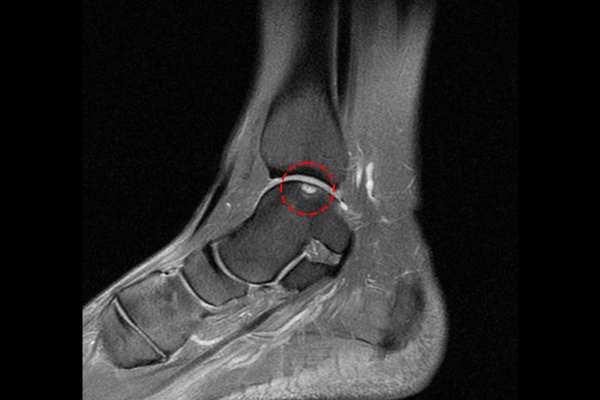

환자분의 발목 상태를 자세히 파악하기 위해서 MRI 촬영을 진행하였고,

MRI에서 발목 거골 부위 연골 손상과 골 괴사가 확인되었기에 발목 거골 골연골병변(박리성, 이단성 골연골염, 연골손상)(t. ankle osteochondral lesion of talus)을 진단하였습니다.